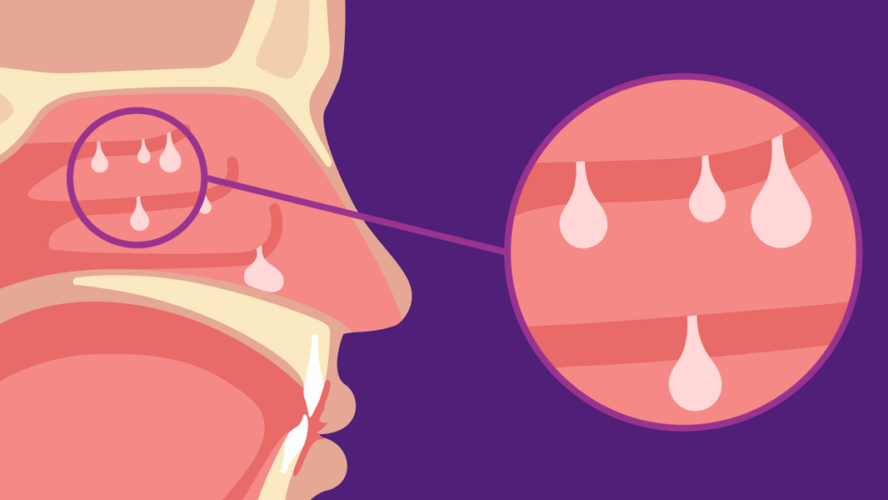

Slide 2: Los pólipos nasales son neoplasias dentro de la nariz o de los senos paranasales. No son cancerosos, pero pólipos grandes podrían: Dificultar la ….